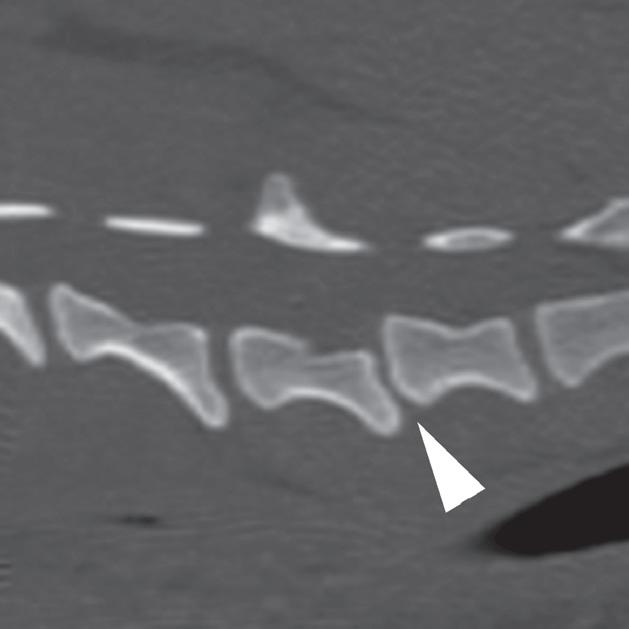

Rycina

3.2.8. Podwichnięcie kręgów szyjnych ze złamaniem wyrostka stawowego (pies) TK i MR

Badania wykonano u 5-letniej samicy mieszańca w typie teriera, która została pogryziona w okolicy szyjnej przez większego psa tego samego dnia, w którym wykonano badania. Podczas wizyty u psa zaobserwowano deficyty neurologiczne z neuroanatomiczną lokalizacją w obrębie C6–T2. Radiogramy przeglądowe ukazały grzbietowe podwichnięcie kręgu C7 względem C6 oraz zwężenie przestrzeni międzykręgowej C6–C7 (a – grot strzałki). Podobne zmiany uwidoczniono na obrazach TK w projekcji strzałkowej i 3D (b, f – grot strzałki). Dodatkowo stwierdzono wieloodłamowe złamanie z przemieszczeniem prawego doczaszkowego wyrostka stawowego kręgu C7 (c–e – strzałka). Dla porównania przedstawiono prawidłowy lewy wyrostek stawowy (f – strzałka). W badaniu MR przestrzeń międzykręgowa C6–C7 była zwężona i wykazywała obniżoną intensywność sygnału w obrazach T2-zależnych (i – strzałka), a przemieszczony materiał dyskowy znajdował się w prawej dobrzusznej części kanału kręgowego (g, h – grot strzałki). W obrazach występują cechy ucisku na rdzeń kręgowy (g–i) oraz zwiększona intensywność sygnału w sekwencji T2-zależnej w obrębie rdzenia na poziomie C6–C7 (h, i), co wskazuje na jego uszkodzenie wewnętrzne. Materiał dyskowy został chirurgicznie usunięty z kanału kręgowego, a podwichnięcie zredukowano i ustabilizowano operacyjnie